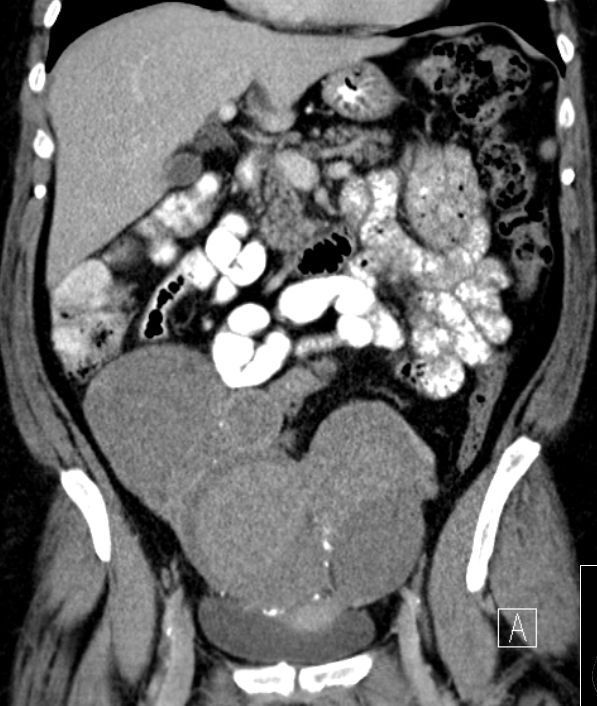

53-jährige Frau mit einem muzinösen Borderlinetumor vom intestinalen Typ.